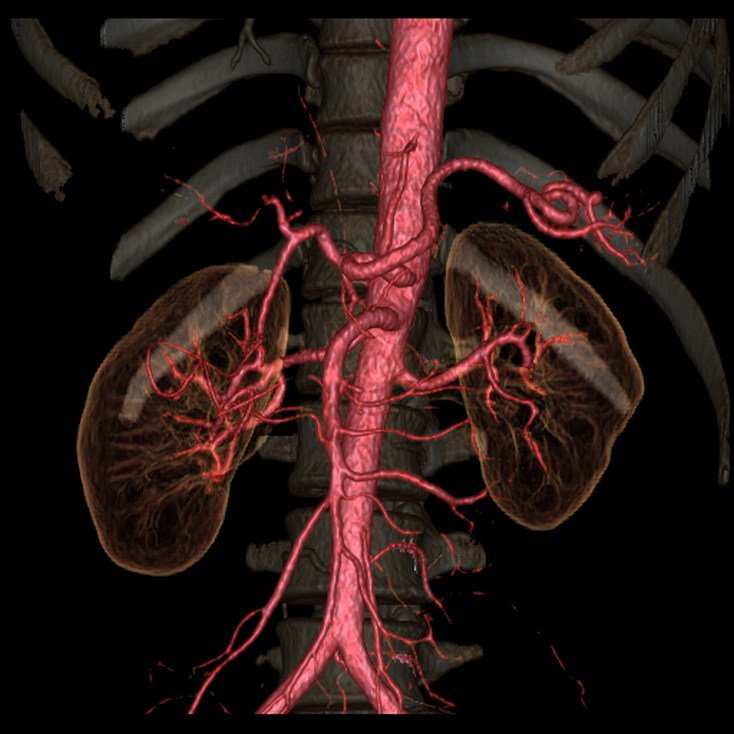

CT Kidney

Kidney Angiography